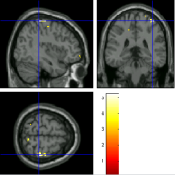

Once the reduced FOV images are available, the proposed pMRI 4D-UWR-SENSE algorithm and its early UWR-SENSE version have been utilized in a final step to reconstruct the full FOV EPI images and compared to the mSENSE Siemens solution. For the wavelet-based regularization, dyadic Symmlet orthonormal wavelet bases [48] associated with filters of length 8 have been used over resolution levels. The reconstructed EPI images then enter in our fMRI study in order to measure the impact of the reconstruction method choice on brain activity detection. Note also that the proposed reconstruction algorithm requires the estimation of the coil sensitivity maps (matrix in Eq. (2)). As proposed in [4], the latter were estimated by dividing the coil-specific images by the module of the Sum Of Squares (SOS) images, which are computed from the specific acquisition of the -space centre (24 lines) before the scans. The same sensitivity map estimation is then used for all the compared methods. Fig. 5 compares the two pMRI reconstruction algorithms to illustrate on axial, coronal and sagittal EPI slices how the mSENSE reconstruction artifacts have been removed using the 4D-UWR-SENSE approach. Reconstructed mSENSE images actually present large artifacts located both at the centre and boundaries of the brain in sensory and cognitive regions (temporal lobes, frontal and motor cortices, …). This results in SNR loss and thus may have a dramatic impact for activation detection in these brain regions. Note that these conclusions are reproducible across subjects although the artifacts may appear on different slices (see red circles in Fig. 5). One can also notice that some residual artifacts still exist in the reconstructed images with our pipeline especially for . Such strong artifacts are only attenuated and not fully removed because of the high level of information loss at .

| mSENSE | 4D-UWR-SENSE | ||

| Axial |  |

|

|

| Coronal | |||

| Sagittal | |||

| Axial |  |

|

|

| Coronal | |||

| Sagittal |